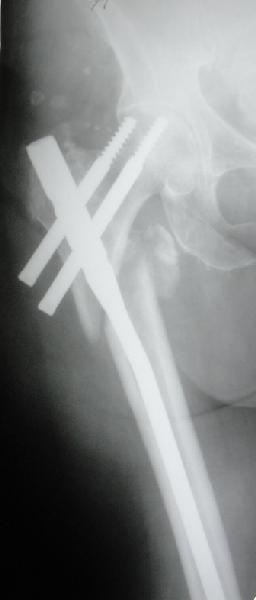

Фиксация * reversed obliquity* подвертельных переломов - дело непростое.

На мой взгляд, причиной телескопирования явилось несоответствие диаметра гамма нэйл с диаметром канала подвертельного отдела бедра: обратите внимание на величину протрузии шеечного винта и величину медиализации дистального фрагмента - они одинаковы, смещение или телескопирование фрагментов происходило до того момента, пока гамма нэйл не упёрся в медиальный кортекс и образовалось пространство между латеральным

кортексом и латеральной поверхностью гвоздя.

Диаметр гаммы в диафизарной части ~11 мм. А диаметр канала, тем более у пожилых с остеопорозом, может быть мм 15. Даже рассверливать обычно не приходится, после формирования широкого канала в вертельной области можно сразу толкать гвоздь, он влетает, как карандаш в стакан. Так что соответствия диаметров не бывает никогда. Однако представленная ситуация случается далеко не каждый раз. Если гвоздь в центральном отломке входит чуть медиальнее верхушки вертела, и идет вдоль передне-латеральной стенки центрального отломка, то все будет хорошо.

В приложении похожий пример, к счастью, пациентка появилась не после, а "за полчаса" до протрузии. Пересинтезировали с исправлением ошибок.